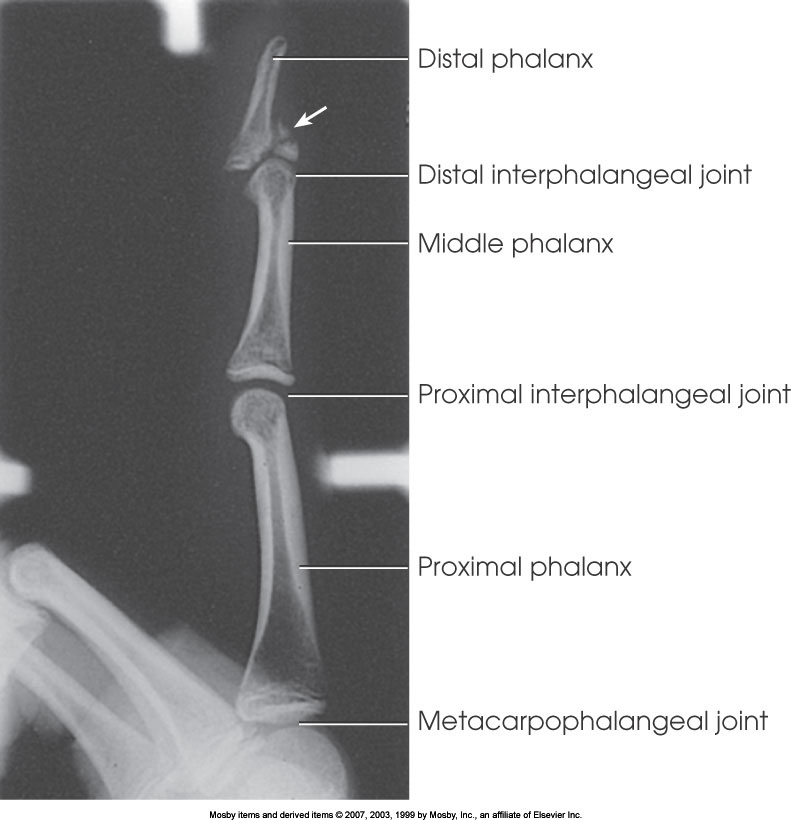

Lateral Finger

What position is demonstrated?